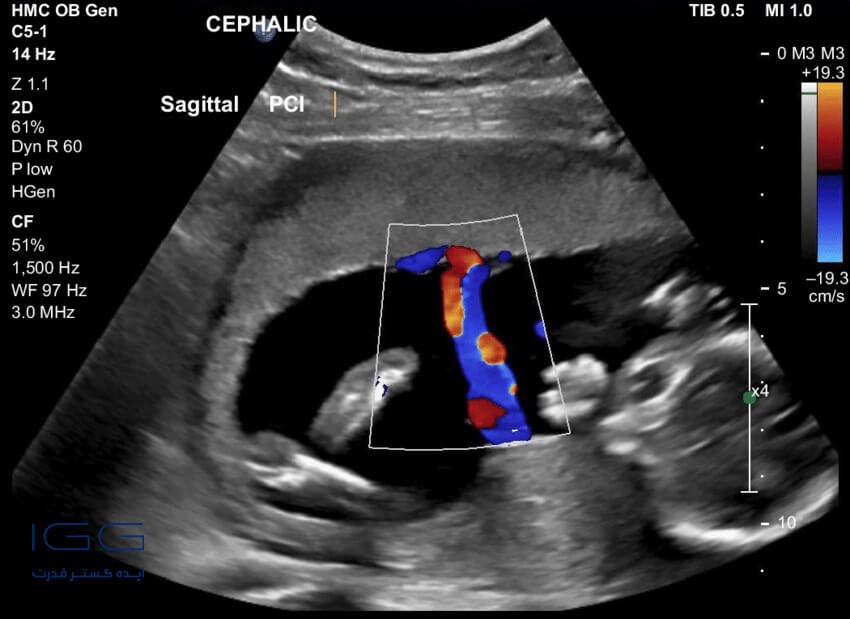

1. سونوگرافی داپلر رنگی

نوع اول، سونوگرافی داپلر رنگی است، یعنی تصاویر با رنگهای متفاوت روی صفحه نمایشگر نشان داده میشوند. در این آزمایش، از یک کامپیوتر مخصوص برای تغییر رنگ تصاویر استفاده میشود. با استفاده از تغییر رنگ، میتوان سرعت یا جهت جریان خون را ارزیابی کرد.